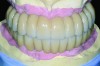

The maxillary prototype was adjusted, polished, and left to function with the mandibular provisional. The definitive maxillary zirconia restoration was then completed from the information provided by the prototype, and the cutbacks for the facial porcelain (Nos. 6 through 11) were done after milling but before sintering. Subsequently, the mandibular prototype was adjusted to the sintered and colored maxillary zirconia framework before the application of porcelain to Nos. 6 through 11 and final glazing (Figure 11). Following this step, the mandibular definitive monolithic zirconia restoration was milled, colored, and sintered. The facial porcelain (Nos. 6 through 11) was applied, and then both maxillary and mandibular restorations were stained and glazed (Figure 12). Both bridges were inserted at the same time (Figure 13 through Figure 15). Minor occlusal adjustments and oral hygiene access was verified and the zirconia surfaces polished. The bridge screws were torqued to 20 Ncm according to the manufacturer’s recommendation, and No. 24 was luted with a provisional cement. Postoperative radiographs were taken (Figure 16).

Fig 12. Extraoral frontal view of the completed maxillary and mandibular articulated zirconia restorations on master casts.

Figure 12